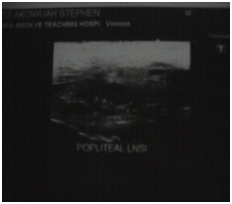

These radiological diagnostic features were suggestive of sickle cell disease with Thoracolumbar spondylodiscitis, likely pyogenic; Bilateral Avascular Necrosis of the femoral head (early on the left); Septic arthritis of the right hip and left shoulder joint; Osteomyelitis of the left 8th and 9th ribs. Doppler Ultrasound of the lower limb revealed the following: The right common femoral and superficial femoral veins were of normal lumen with good wall to wall compressibility, good colour doppler and spectral wave form properties. The right popliteal and posterior tibial veins however showed extensive echogenic intraluminal-filling defect with resultant loss of wall-to-wall compressibility (percentage stenosis 76%). The accompanying arteries were of normal size and caliber and showed good colour doppler and spectral properties. There was thickening of the subcutaneous tissue with dilated fluid channels seen in the right foot. Inguinal as well as popliteal lymph nodes with retention of their fatty hilum noted averaging 0.9*0.5cm. Also noted was a 1.4*0.9*1.5cm (volume about 1.0ml) anechoic collection with low-level internal echoes at the medial aspect of the proximal thigh muscles; suggestive of inflammatory changes. Based on the Doppler findings a clinical diagnosis of Right Popliteal and Posterior Tibial Vein Thrombosis with Pyomyositis in a Sickle Cell Disease patient was considered and patient was subsequently administered subcutaneous Enoxaparin 40mg daily as well as Warfarin 3mg nocte, IV Clindamycin 150mg qid, IV Ciprofloxacin. After 2 days of Warfarin and Enoxaparin, INR and PT were repeated and results were 1.1 and 15.1s respectively. The child was followed up closely for four weeks and subsequently discharge. A repeat Doppler finding revealed a completely resolved thrombus with no evidence of DVT.